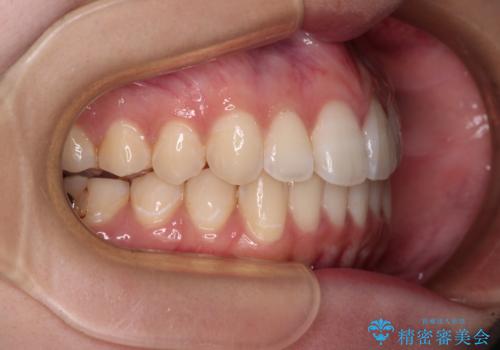

上下前歯の突出感とデコボコを気にして来院された患者様です。

インビザラインによる上下歯列の側方拡大と後方移動、必要に応じてIPR(歯と歯の間を削る)によりスペースの獲得により歯列を整えることとしました。

治療途中、出産や転居があり、2年ほど治療期間が長くなってしまいましたが、前歯の歯並びや飛び出した感覚を無事に改善させることができました。